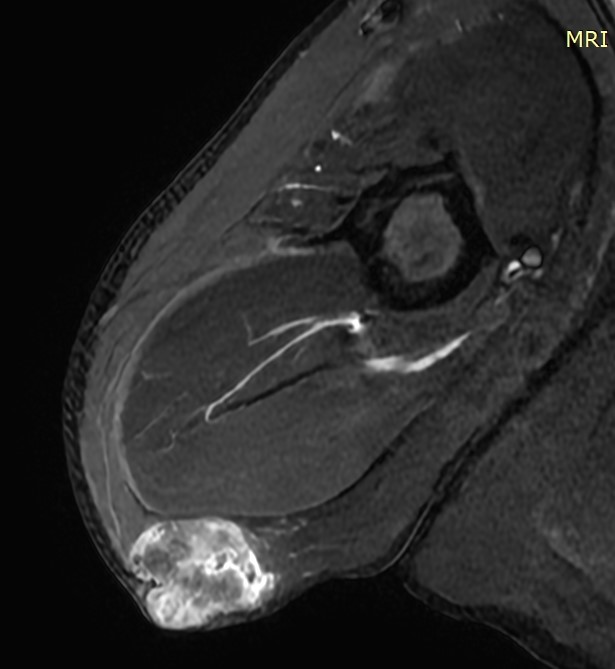

MRI μηροβουβωνικής πτυχής με σκιαγραφικό, που αναδεικνύει μαλακοτισθενή μάζα εκφυόμενη από τη μεγάλη σαφηνή φλέβα (Ευγενική παραχώρηση Dr. V. Penopoulos)